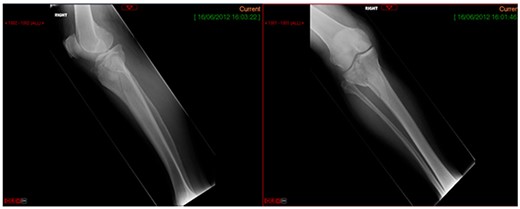

CASE 1

A 68-year-old gentleman who was diagnosed with a Schatzker type VI fracture having fallen 3 m from a ladder (Figs 1 and 2). The injury was closed and neurovascularly intact. The patient was monitored for signs of compartment syndrome. He rapidly developed significant fracture blisters that persisted for over 2 weeks despite regular dressing care. He was deemed too high risk for acute operative intervention because of a high risk of wound complications. Following a multidisciplinary team discussion, he was managed in a cast then a knee brace, mobilising non weight bearing for 12 weeks, at which point the fracture was seen to be healing in a valgus malalignment. The patient was allowed to partially weight bear and received physiotherapy. He was reviewed regularly until fracture had united (Fig. 3). At 8 months post-injury, the patient underwent total knee arthroplasty utilizing a Depuy Synthes (Warsaw, In) PFC Sigma TC3 tibial metaphyseal sleeve and stem, and femoral component without sleeve or stem (Fig. 4). The patient was reviewed post-operatively in clinic at 6 months, the wound had fully healed and the range of motion was 0°–120°. The patient’s pain was significantly reduced, and they were independently mobile. They were kept under annual review and seen at 5 years post-operatively with an Oxford Knee score of 35; the patient used no walking aids and was pain free at rest or during normal walking, with the radiograph demonstrating good osseointegration. The latest follow-up at 8 years revealed no radiographical change in implant (Fig. 5).